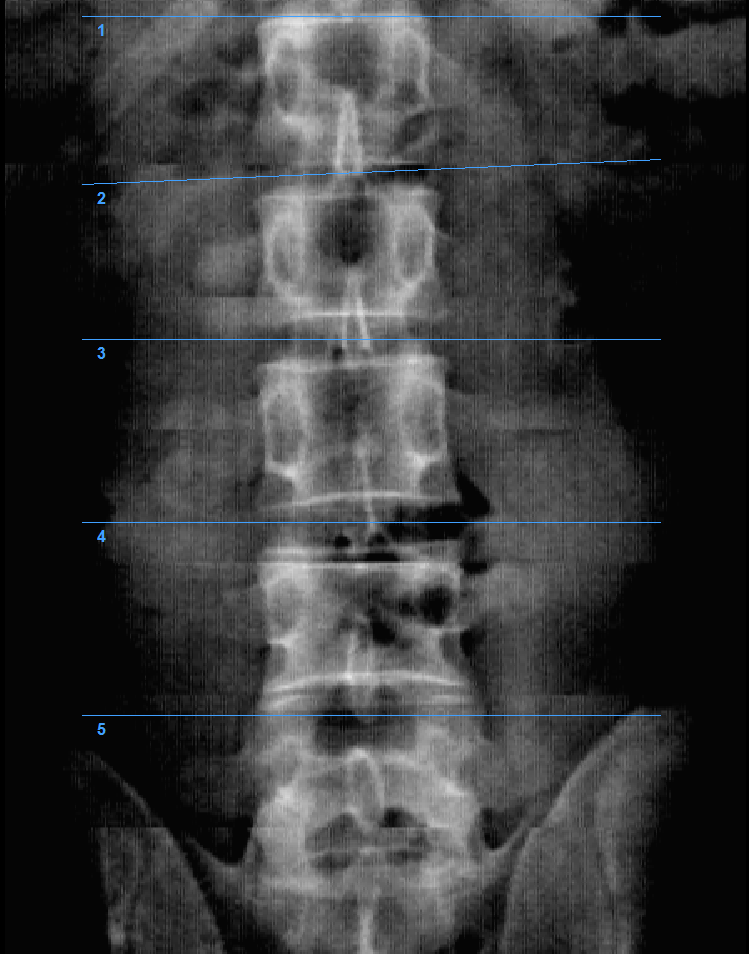

Денситометр Medikors InAlyzer-AIR оснащено 64-канальным двухэнергетическим рентгеновским датчиком, основанным на технологии веерных лучей, и позволяет получать 64 ряда данных за одно рентгеновское обследование, обеспечивая получение данных более высокого разрешения за более короткий период времени по сравнению с системами, основанными на технологии остронаправленных лучей и позволяющими получать только 1 ряд данных за одно рентгеновское обследование.

Денситометр InAlyzer-AIR, разработанный компанией Medikors, использует технологию рентгеновского излучения. Он пропускает сфокусированный рентгеновский луч через анализируемый объект – кость. Измеряется степень поглощения рентгеновских лучей, и эта информация используется для расчёта плотности и состава. Эта технология позволяет неинвазивно измерять минеральную плотность костной ткани и может использоваться для точной и достоверной диагностики остеопороза или мониторинга эффективности лечения.

- Высокое разрешение и быстрый анализ